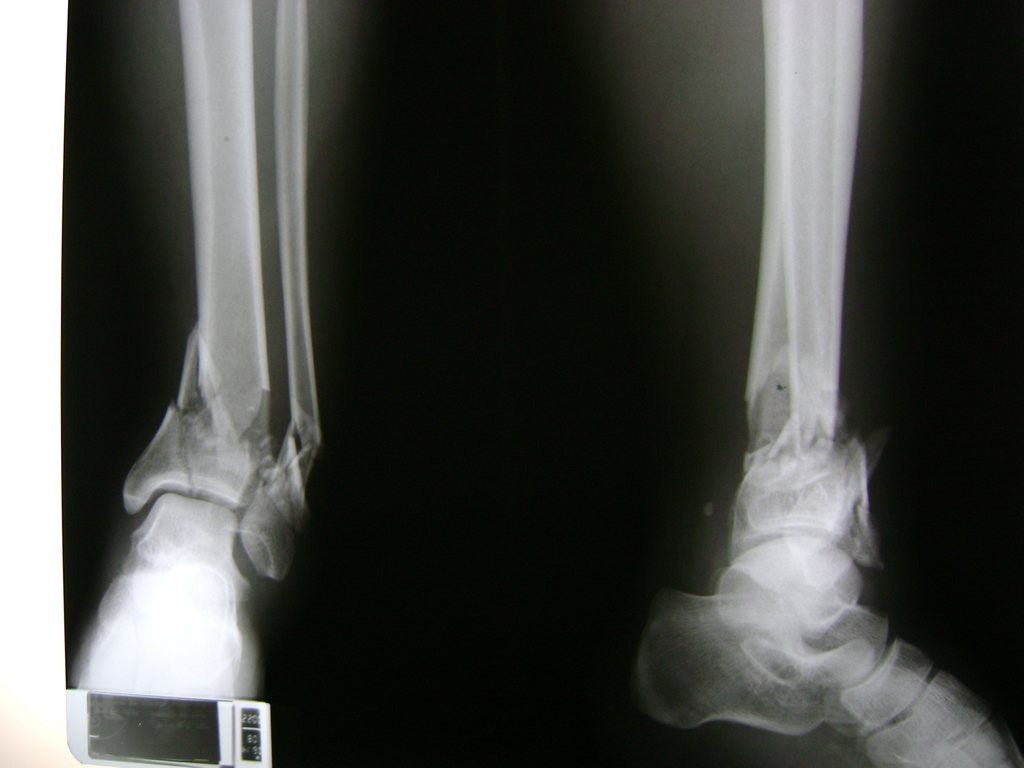

Una fractura de tobillo es la rotura de uno o más de los huesos del tobillo. Estas fracturas pueden ser:

Algunas fracturas de tobillo pueden requerir cirugía si:

- Los extremos de los huesos están desalineados entre sí (desplazados).

- La fractura se extiende hasta la articulación del tobillo (fractura intra-articular).

Cuando se necesita cirugía, es probable que esta implique el uso de clavijas de metal, tornillos o placas para sostener los huesos en su lugar mientras la fractura se consolida. Los elementos de soporte pueden ser temporales o permanentes.